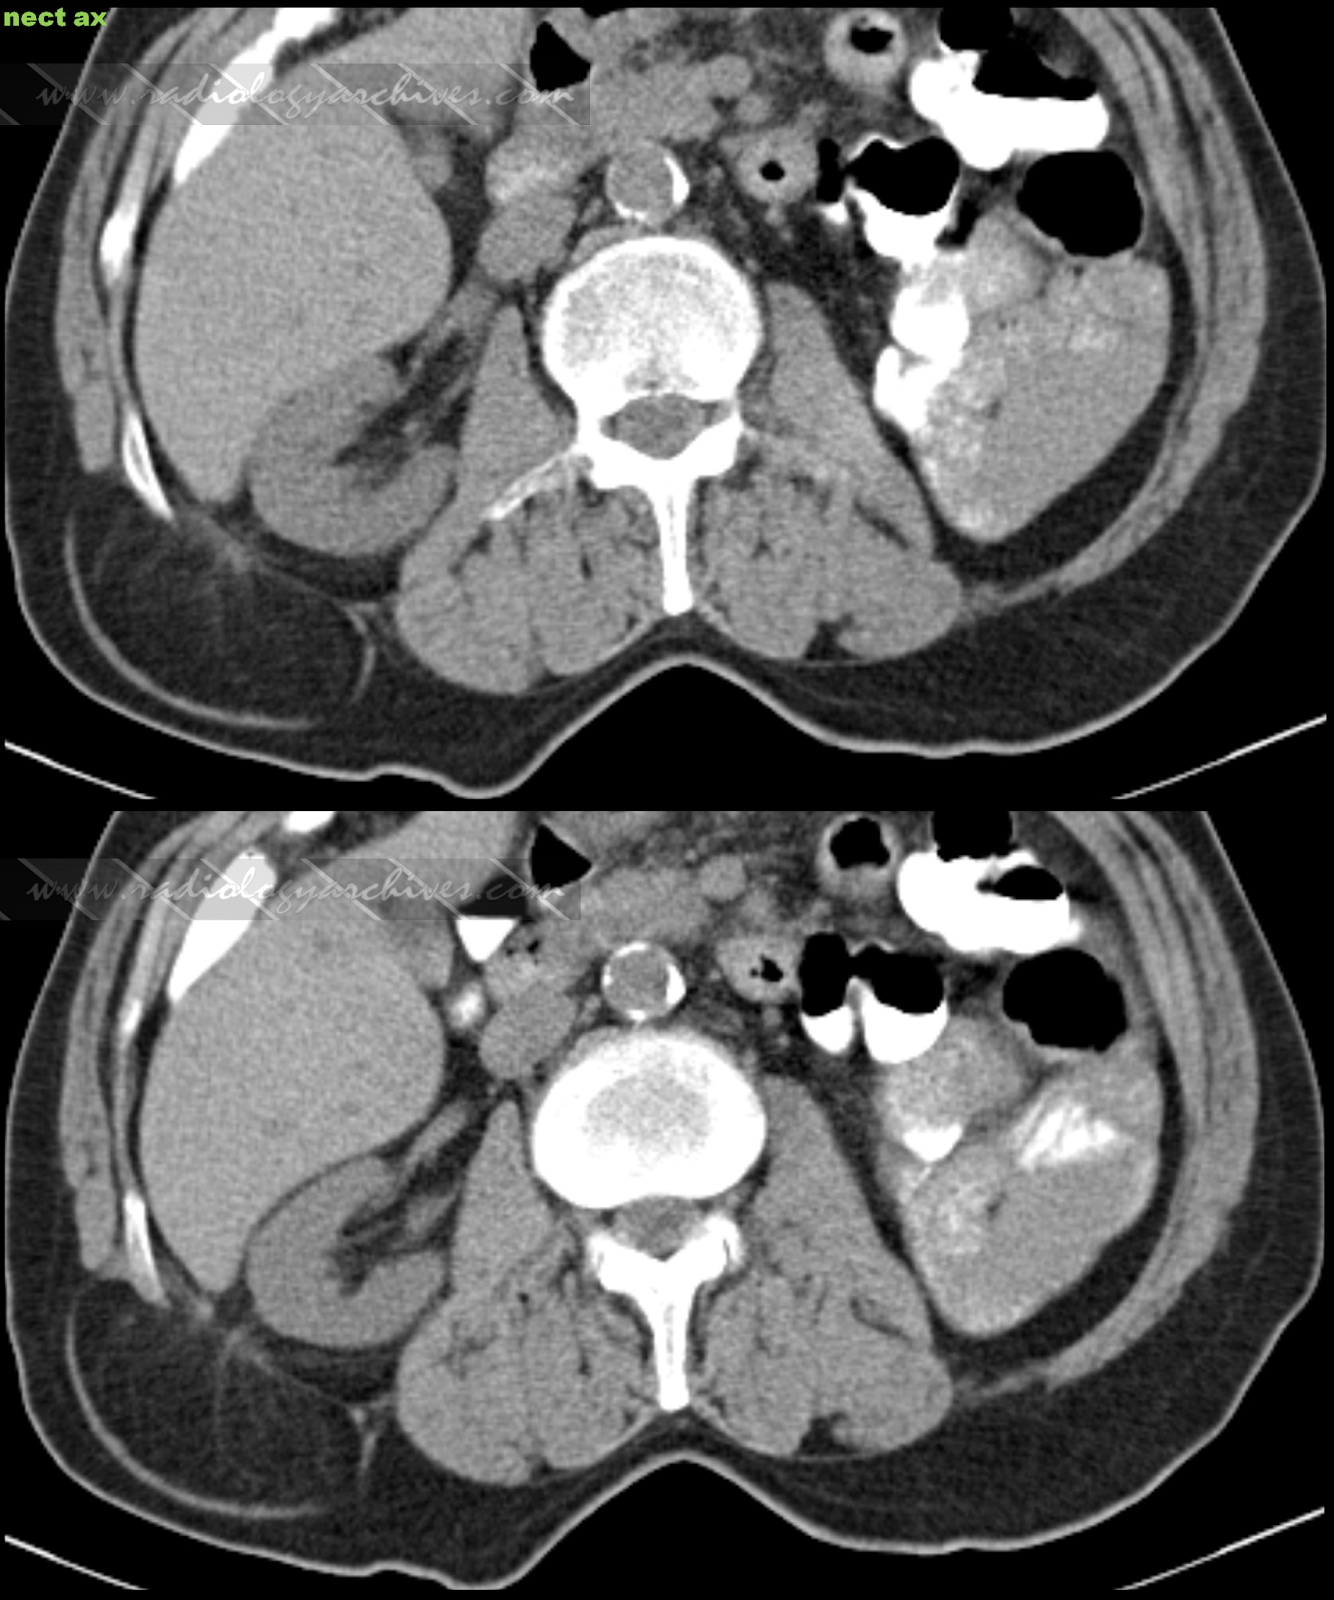

From www.radiologyarchives.com

Radiology Archives Οσφυϊκή Κήλη (Οσφυοκήλη Grynfeltt Lesshaft) Lumbar Hernia Grynfeltt grynfeltt's lumbar hernia is a rare abdominal wall pathology with around. lumbar hernias occur through defects in the lumbar muscles or the posterior fascia, below the 12 th rib and above the iliac crest. the aim of the study was to describe the transabdominal laparoscopic. Lumbar Hernia Grynfeltt.

CECT axial section showing GrynfeltLesshaft's hernia with 56 mm defect Lumbar Hernia Grynfeltt grynfeltt's lumbar hernia is a rare abdominal wall pathology with around. lumbar hernias occur through defects in the lumbar muscles or the posterior fascia, below the 12 th rib and above the iliac crest. the aim of the study was to describe the transabdominal laparoscopic. Lumbar Hernia Grynfeltt.